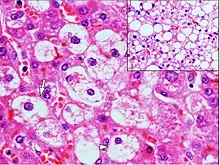

Micrograph demonstrating marked (macrovesicular) steatosis in non-alcoholic fatty liver disease. Masson's trichrome stain. | |

Steatosis reflects an impairment of the normal processes of synthesis and elimination of triglyceride fat. Excess lipid accumulates in vesicles that displace the cytoplasm. When the vesicles are large enough to distort the nucleus, the condition is known as macrovesicular steatosis; otherwise, the condition is known as microvesicular steatosis. While not particularly detrimental to the cell in mild cases, large accumulations can disrupt cell constituents, and in severe cases the cell may even burst.

Histology

Histologically, steatosis is physically apparent as lipid within membrane bound liposomes of parenchymal cells.[2] When this tissue is fixed and stained to be better viewed under a microscope, the lipid is usually dissolved by the solvents used to prepare the sample. As such, samples prepared this way will appear to have empty holes (or vacuoles) within the cells where the lipid has been cleared. Special lipid stains, such as Sudan stains and osmium tetroxide are able to retain and show up lipid droplets, hence more conclusively indicating the presence of lipids. Other intracellular accumulations, such as water or glycogen, can also appear as clear vacuoles, therefore it becomes necessary to use stains to better determine what substance is accumulating.

- Histological section of a mouse's liver showing severe steatosis. The clear vacuoles contained lipid in life; however, histological fixation caused it to be dissolved and hence only empty/clear spaces are seen.

- Micrograph of fatty liver showing lipid steatosis. H&E stain.

- Steatosis with a centrilobular pattern, which is the general tendency for steatosis in adults.[11]